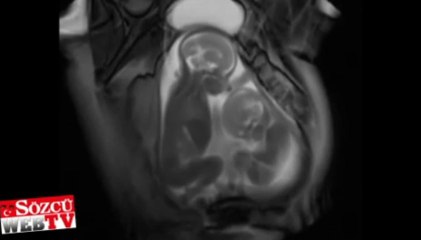

Meksika'da yaşayan bu annenin daha doğmamış bebeği dans etmeye bayılıyor! Telefondan çalan müzik ile dans etmeye başlayan anne karnındaki bebeğin o anları...